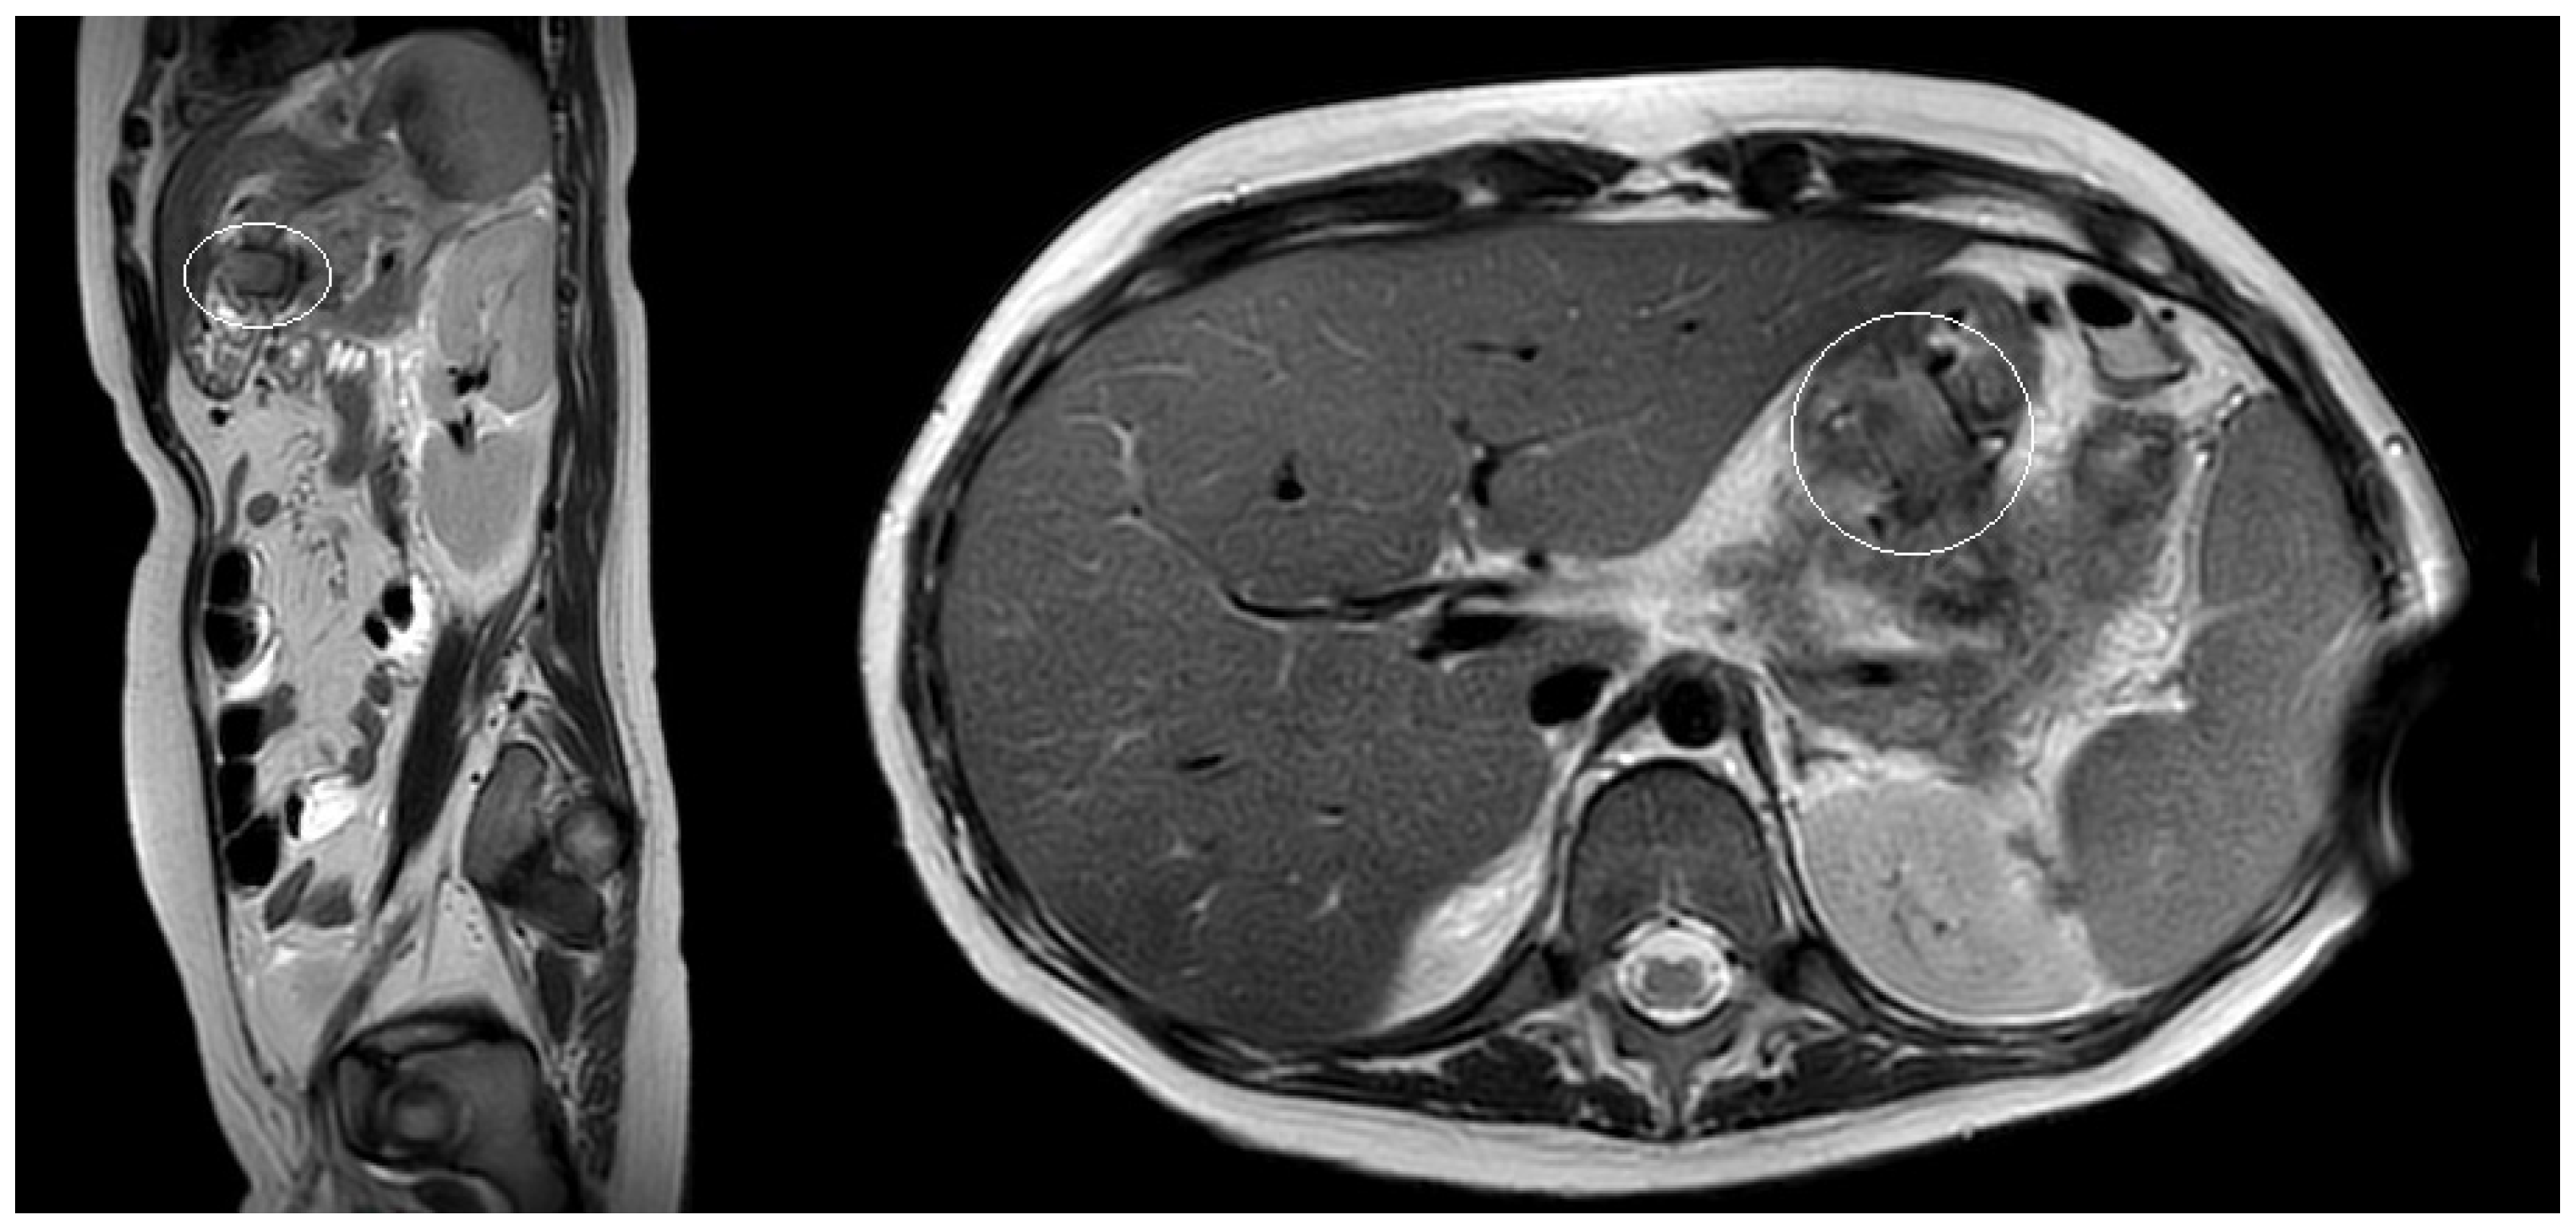

3.1.2. Patient n°2

A 15-year boy was affected by B-acute lymphoblastic leukemia and severe coagulopathy; he developed a chemotherapy-induced acute cholecystitis, acute pancreatitis complicated by septic shock and PFC. At MRI the major diameter of the collection was 12 cm (Figure 4). After unsuccessful attempts of conservative treatment, the boy underwent two different attempts of EUS-guided trans-gastric pseudocyst puncture and liquid aspiration, within a month between the two procedures. few days after the second one, the PFCs persisted and the boy still presented abdominal pain and fever. As the need to not delay chemotherapy was pressing, the patient underwent EUS-guided cystogastrostomy and EC-LAMS positioning as a rescue procedure. Post-operative course was uneventful. MRI performed 14 days after the procedure showed a significant reduction of the pseudocyst, which was no longer visible on the ultrasound performed right before its removal. EC-LAMS stayed in place for a total of 28 days and was endoscopically removed, without any intra-operative or post-operative complication.

Figure 4.

Patient n°2 MRI. Pseudocyst with maximum diameter 12 cm in the left hypochondrium in close proximity to the posterolateral wall of the stomach.

During 1 year and 3 month of follow-up, no recurrence of acute pancreatitis and pseudocyst occurred; the patient died after lymphoma relapse.